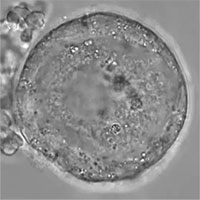

Tế bào trứng của con người có thể tồn tại đến 50 năm

Trứng của con người có thể tồn tại trong một khoảng thời gian dài. Khi một bé gái sinh ra, hệ sinh sản đã phát triển tất cả những quả trứng mà bé gái sẽ có trong suốt quãng đời còn lại.